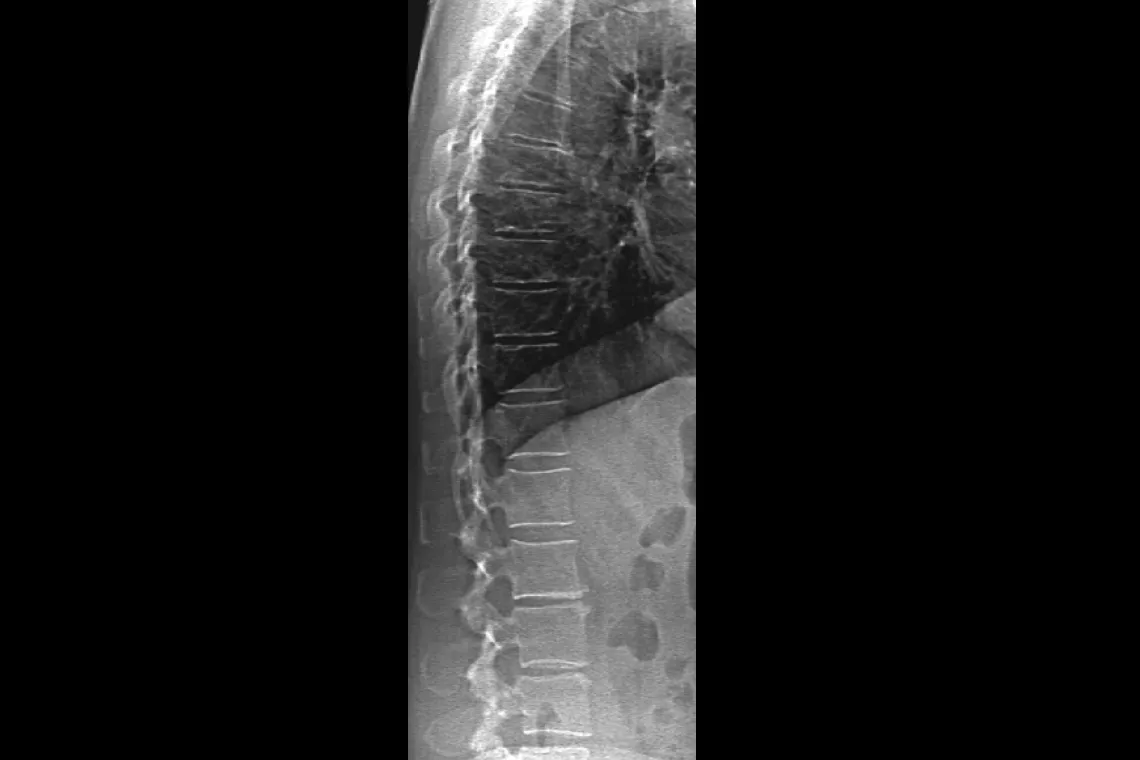

Horizon DXA produces radiographic quality images of the entire femur for assessment of potential atypical femur fractures.31 A quick, 15-second scan reveals cortical thickening of the bone, making it fast and easy to monitor the effects of bisphosphonate therapy over time.

Visualise calcified plaque in the abdominal aorta, which may be a significant indication of heart disease and stroke, two of the leading causes of death in men and women.

Assess fracture risk by combining an accurate measurement of bone density with high-resolution vertebral imaging. You can identify spine fractures with a low-dose, single-energy image in 10 seconds.